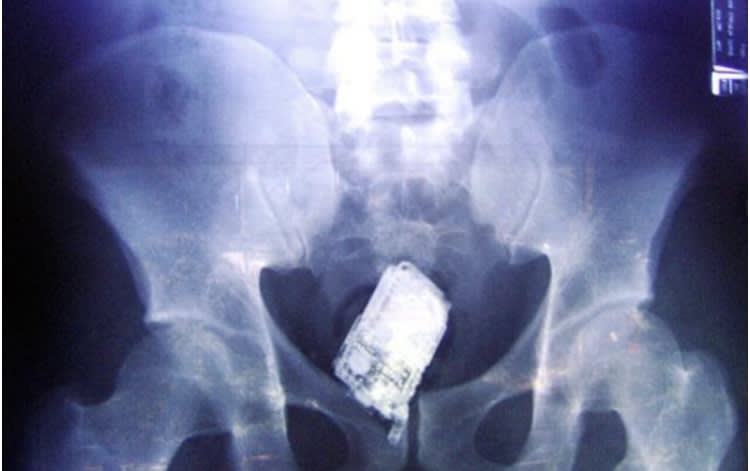

Un petit téléphone portable pour le plaisir :

ça y est, j'ai enfin retrouvé mon téléphone.!

AHHHHH le mode vibreur. Tu m'appelles ? -)))